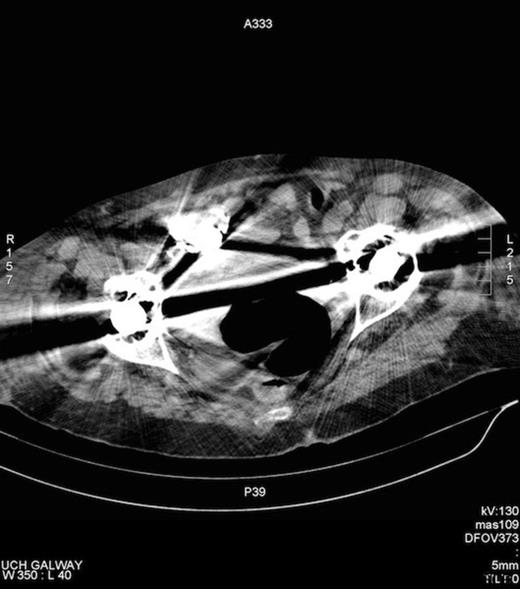

She denied bowel symptoms. Examinations in the SOPD revealed an erythematous, tender swelling in the right groin, with an opening exuding malodorous fluid that had caused marked skin excoriation. On abdominal examination she was tender to palpation in the right groin and guarding and rebound tenderness were absent in the right iliac fossa. There was no clinical evidence of sepsis. A colocutaneous fistula was suspected clinically, when over several days the discharge became faeculent. A CT fistulogram showed a fistulous tract communicating with the caecum and the peritoneal cavity (Figures 1 and 2). She subsequently underwent an elective laparotomy for a planned right hemicolectomy, on a presumptive diagnosis of either a caecal tumour or inflammatory process.

CT fistulogram post injection of contrast via the groin opening. Contrast can be seen to fill the caecum, confirming the presence of a fistula.